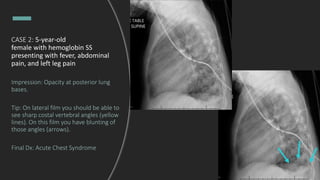

CASE 2: a 5-year-old female with

hemoglobin SS presenting with

fever, abdominal pain, and left leg

pain.

CXR is ordered. What do you see?

CASE 2: 5-year-old

female with hemoglobin SS

presenting with fever, abdominal

pain, and left leg pain

Impression: Opacity at posterior lung

bases.

Tip: On lateral film you should be able to

see sharp costal vertebral angles (yellow

lines). On this film you have blunting of

those angles (arrows).

Final Dx: Acute Chest Syndrome